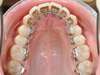

Après Orthodontie linguale Invisible Incognito, un fil est collé sur la face linguale des dents pour stabiliser le résultat.